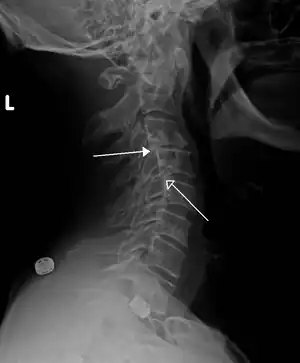

| Grade 1 retrolistheses of C3 on C4 and C4 on C5 | |

A retrolisthesis is a posterior displacement of one vertebral body with respect to the subjacent vertebra to a degree less than a luxation (dislocation). Retrolistheses are most easily diagnosed on lateral x-ray views of the spine. Views where care has been taken to expose for a true lateral view without any rotation offer the best diagnostic quality.